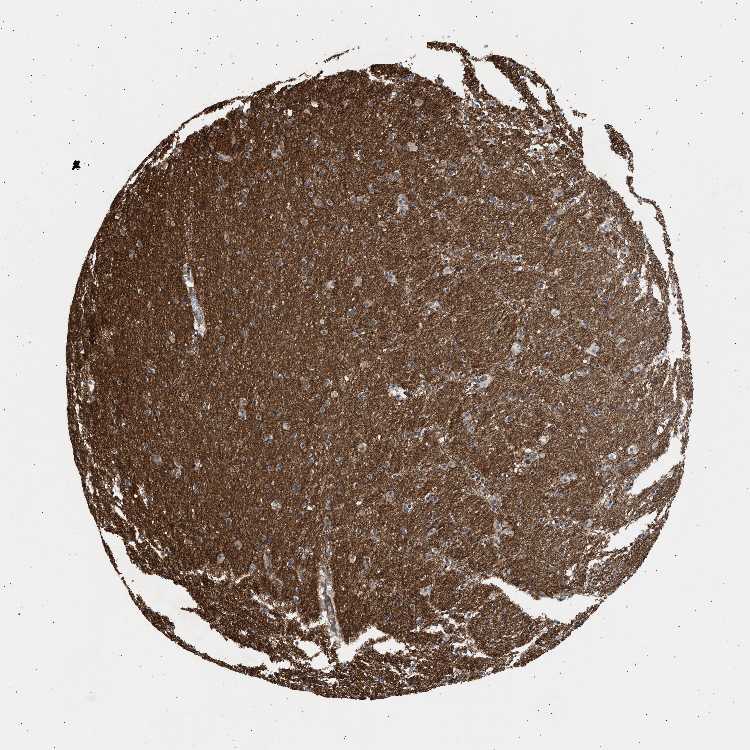

HIPPOCAMPUS - Antibody stainingi

Antibody staining in the annotated cell types in the current human tissue is reported as not detected, low, medium, or high, based on conventional immunohistochemistry profiling in selected tissues. This score is based on the combination of the staining intensity and fraction of stained cells.

Each image is clickable and will lead to virtual microscopy that enables deeper exploration of all samples and also displays staining intensity scores, fraction scores and subcellular localization as well as patient and tissue information for each sample.

Antibody HPA007216

Glial cells Not detected

Neuronal cells Medium